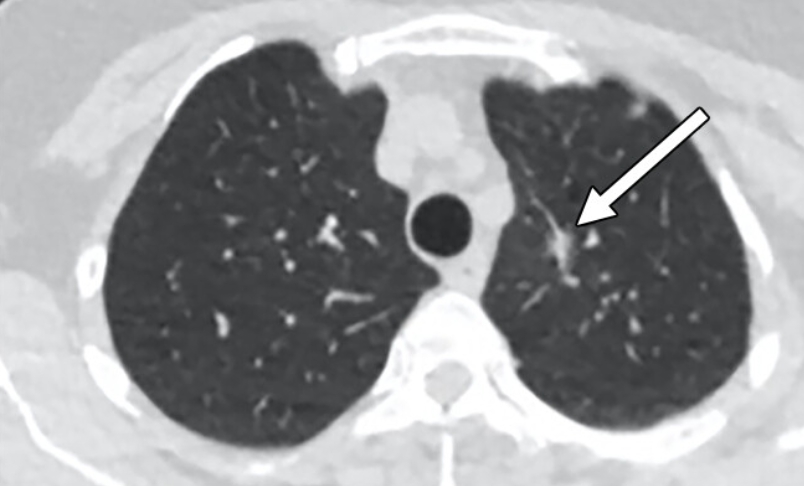

흉부 엑스레이 결절음영

결절음영이란 말은 엑스레이에서 ‘혹처럼 보이는 부분’을 뜻해요. 작게 하얗게 보이는 점, 혹은 둥근 모양의 그림자가 결절음영입니다. 이게 보이면 대부분은 오래된 염증, 흉터, 석회화(염증이 낫고 남은 흔적)일 때가 많아요.

하지만 간혹 크기가 크거나 모양이 울퉁불퉁한 경우엔 폐암 같은 질환을 의심하기도 합니다. 그래서 보통은 “추적 관찰”을 권해요. 6개월 또는 1년 뒤 다시 찍어서 변화가 없는지 보는 거죠. 제 지인 중 한 분도 건강검진에서 결절음영이 나와서 놀랐지만, 재검 때는 흔적만 남고 없어졌어요. 그때 이후로는 주기적으로 검사받는 걸 잊지 않으신다고 하더라구요.